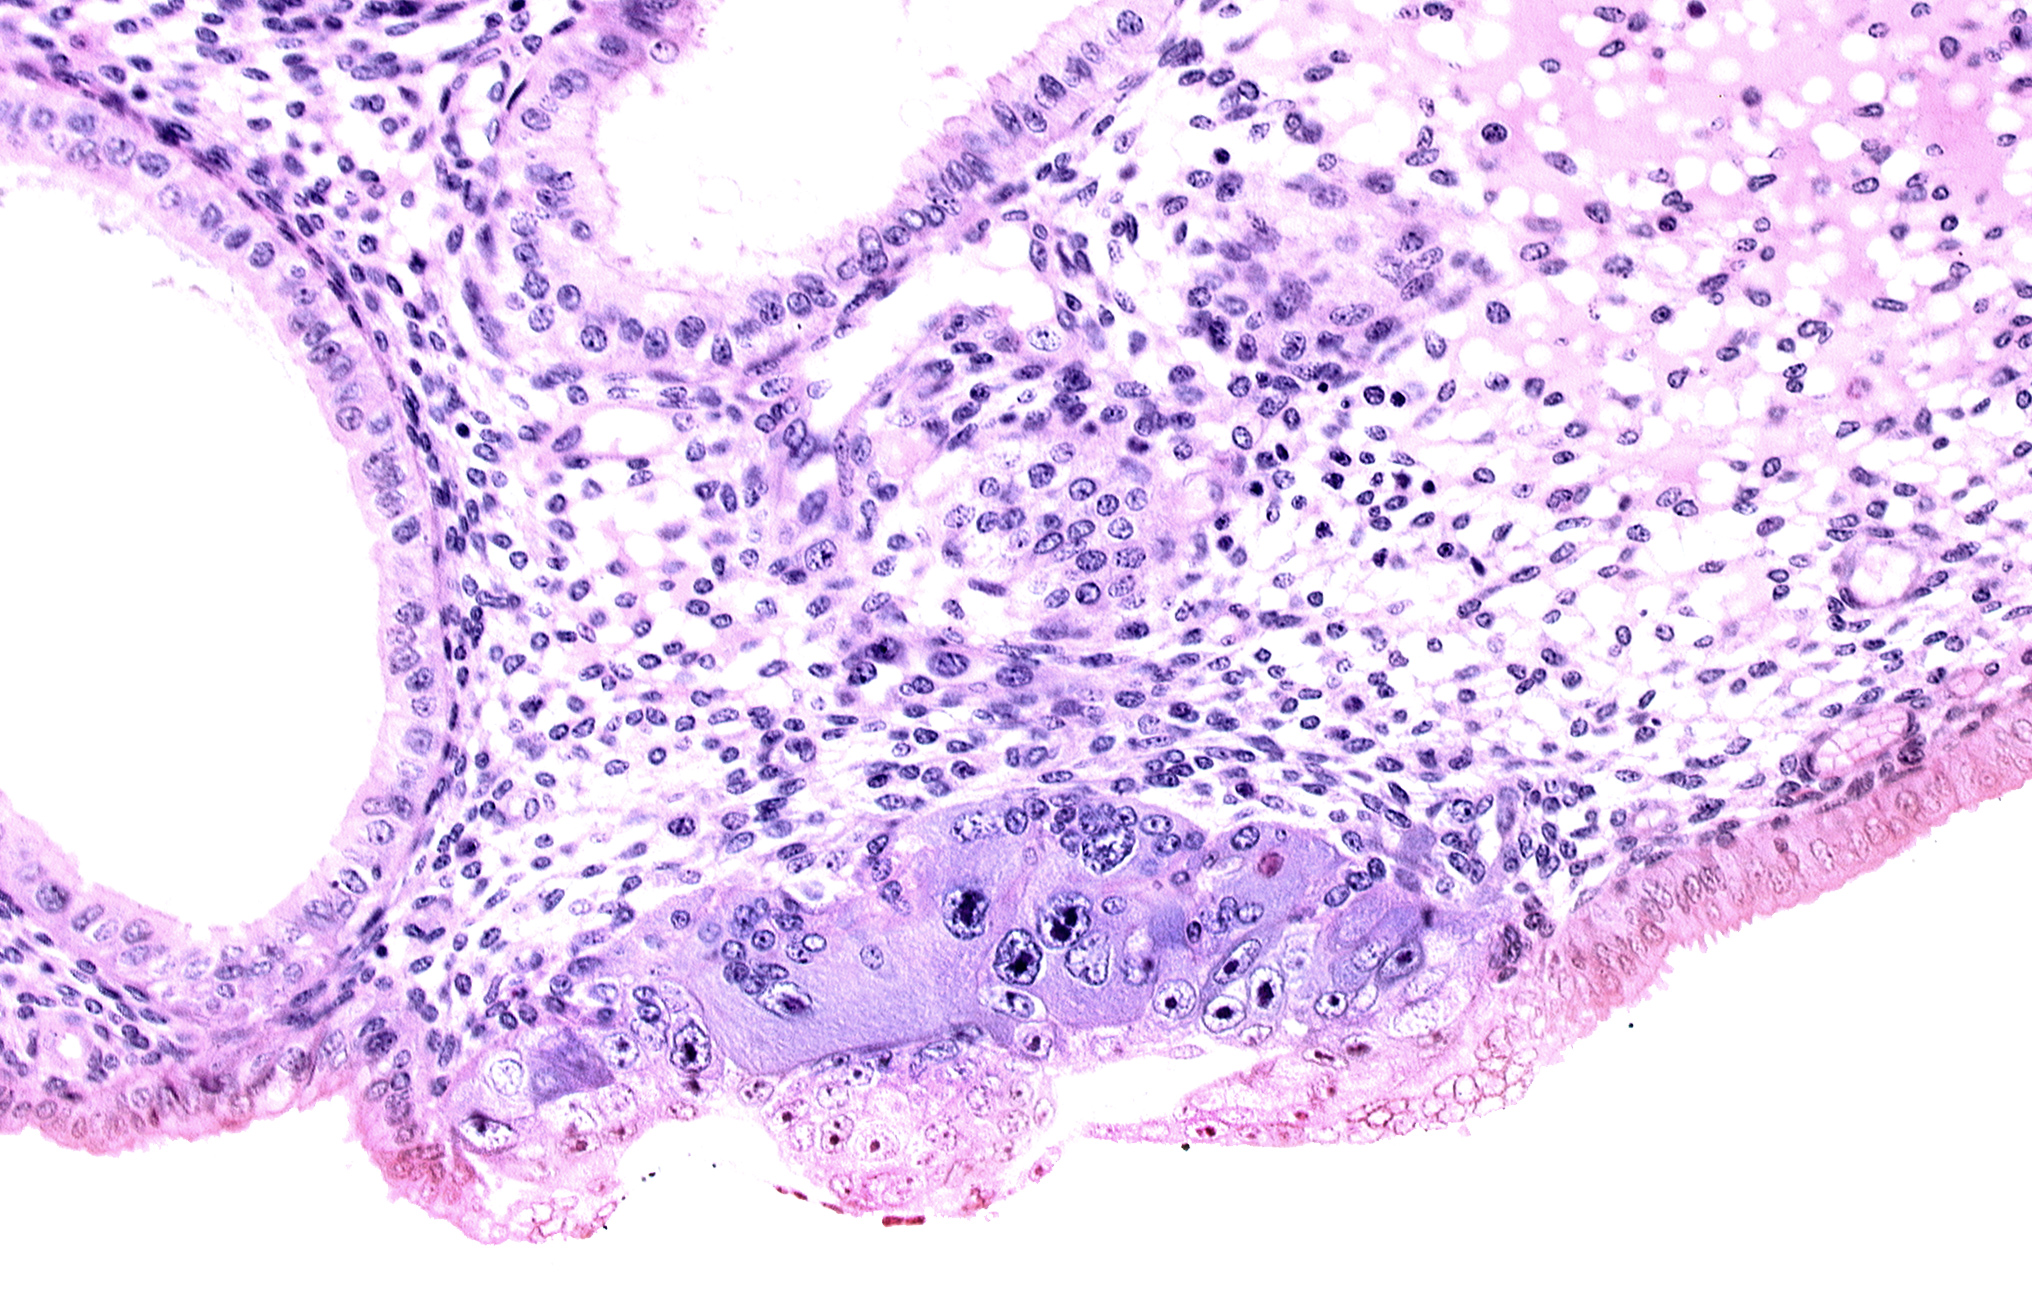

Carnegie Embryo #8020 | Location: 06-02-03

Keywords: blastocystic cavity (blastocoele), embryonic disc, endometrial sinusoid, membranous trophoblast at abembryonic pole, syncytiotrophoblast / decidua interface